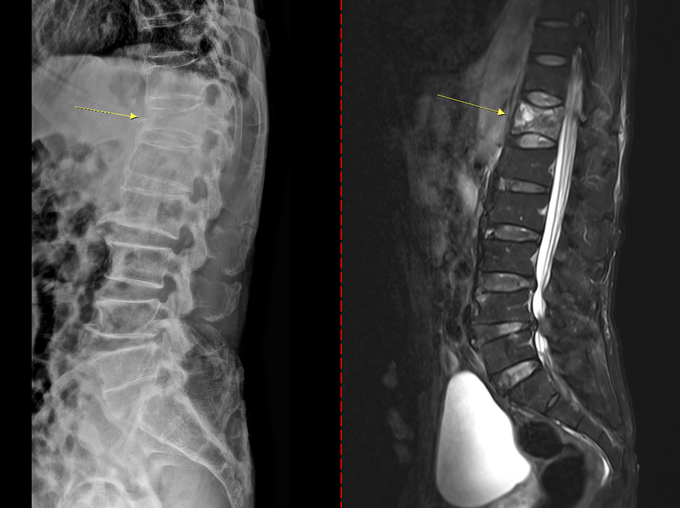

골다공증이 진행되면 가벼운 충격에도 손목이나 대퇴골(엉덩이뼈) 골절이 발생할 수 있다. 특히 대퇴골 골절은 고령 환자에서 수술 후 합병증과 장기 입원, 사망률 증가와 밀접하게 연관된 중증 질환이다. 척추 압박골절이 생기면 등이 굽거나 키가 줄어들고, 만성 통증과 보행 장애로 이어져 활동량 감소와 근력 저하, 추가 골절이라는 악순환을 초래할 수 있다.